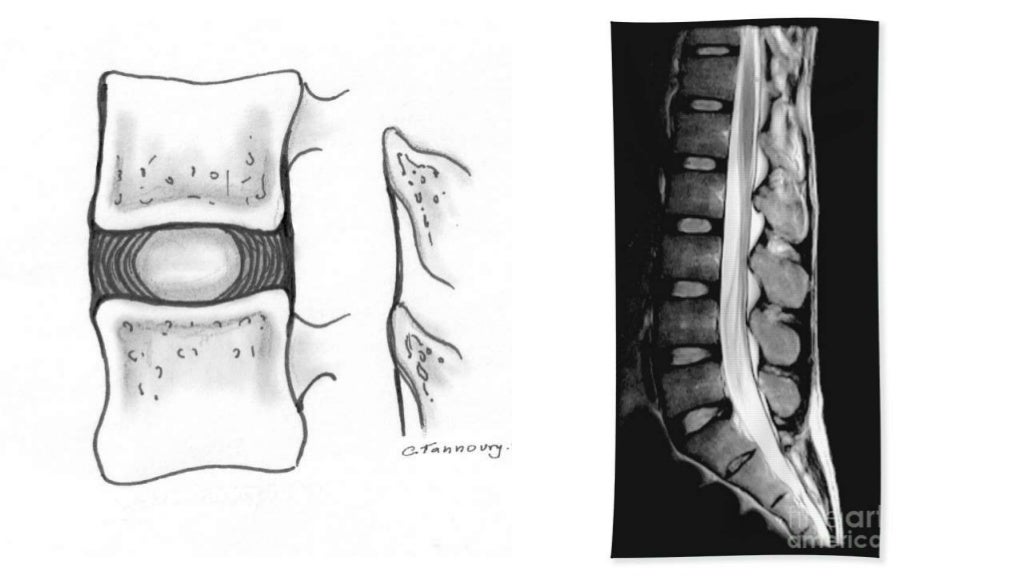

Imaging of lumbar spondylosis Lumbar Spondylosis And Golf It usually causes pain in your lower back. While golf is accessible to athletes of all fitness levels, without the proper muscular conditioning and techniques, golfing may lead to severe lower back pain. I have received pt for both lumbar spondylolisthesis and knee arthritis via doctors’ prescriptions and thus paid for by medicare. Spondylolysis is caused by tiny cracks where. Lumbar Spondylosis And Golf.

Lumbar Spondylosis, Spondylolisthesis and Radiculopathy Lumbar Spondylosis And Golf While golf is accessible to athletes of all fitness levels, without the proper muscular conditioning and techniques, golfing may lead to severe lower back pain. Middle back (thoracic) pain from golf and upper back pain from golf may also occur without warning, even on the golf course. I have received pt for both lumbar spondylolisthesis and knee arthritis via doctors’. Lumbar Spondylosis And Golf.

Imaging of lumbar spondylosis Lumbar Spondylosis And Golf While golf is accessible to athletes of all fitness levels, without the proper muscular conditioning and techniques, golfing may lead to severe lower back pain. It’s vital to adjust your swing to minimize strain on your back. It usually causes pain in your lower back. Middle back (thoracic) pain from golf and upper back pain from golf may also occur. Lumbar Spondylosis And Golf.

Imaging of lumbar spondylosis Lumbar Spondylosis And Golf It’s vital to adjust your swing to minimize strain on your back. It usually causes pain in your lower back. I have received pt for both lumbar spondylolisthesis and knee arthritis via doctors’ prescriptions and thus paid for by medicare. While golf is accessible to athletes of all fitness levels, without the proper muscular conditioning and techniques, golfing may lead. Lumbar Spondylosis And Golf.